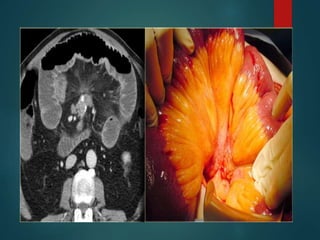

Pseudomyxoma peritonei…

• Is the result of a mucinous producing tumor

of the appendix, ovary,pan etc which presents as

a mucocele and spreads to the peritoneal cavity.

• A typical feature…Septation

..Discrete wall

.. Scalloping surface of the

liver and spleen.

• Unlike peritoneal metastases, there are no

tumor nodules.

• There may be some calcifications.

• #10 1. It is a clinical syndrome, characterized by recurrent and recalcitrant voluminous mucinous ascites due to surface growth on the peritoneum without significant invasion of underlying tissues. 2.A distinctive CT appearance is produced by pseudomyxoma peritonei in which the peritoneal surfaces become diffusely involved with large amounts of mucinous material. Although there is continued debate regarding the site of origin of pseudomyxoma peritonei, clinicopathologic studies suggest that the vast majority of cases arise from primary mucinous adenomas of the appendix, with the ovaries being secondarily involved (79,231,248,326). Although a more benign form (disseminated peritoneal adenomucinosis) and a more malignant form (peritoneal mucinous carcinomatosis) of the disease have been described, the imaging findings of the two forms overlap (22). CT findings include low-attenuation masses with discrete walls or diffuse intraperitoneal low-attenuation material that may contain septations and often causes scalloping of the hepatic, splenic and mesenteric margins (58,177,206,263,287,308,324) (Figs. 16-87, 16-88, 16-89). Calcifications are not uncommon in patients with large volume disease (177), particularly after chemotherapy (176,287). If the walls of the cystic masses are thin, the CT appearance may be similar to that produced by loculated ascites. Scalloping of the liver, spleen and mesenteric margins by extrinsic pressure of the gelatinous masses and failure of the bowel loops to “float” to the anterior abdominal wall may be useful in differentiating pseudomyxoma peritonei from ascites (263). P.1142